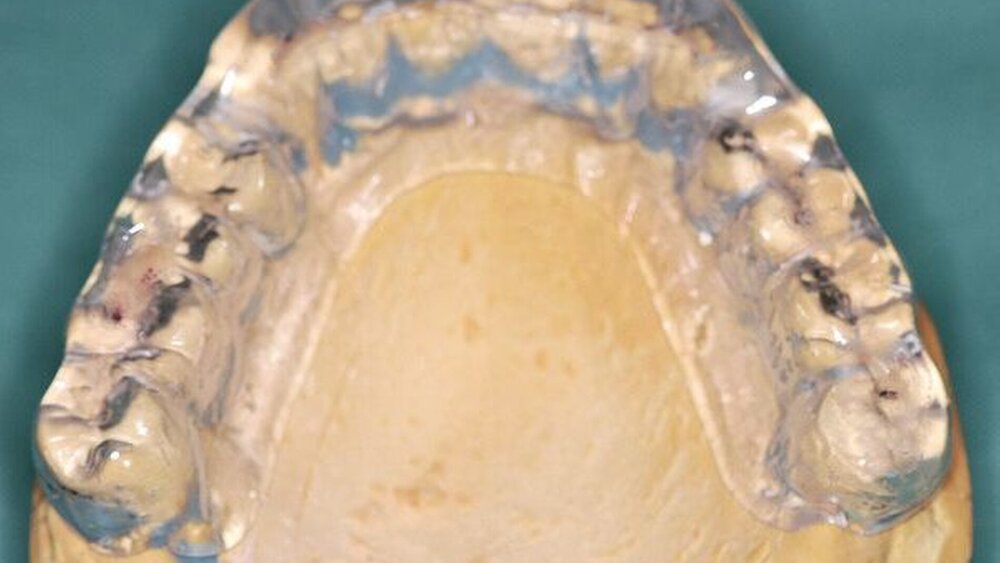

In der folgenden Sitzung wurden Versorgungsabformungen des Ober- und des Unterkiefers unter Verwendung eines A-Silikons angefertigt. Danach wurden alle verblockten Kronen sowie die Brücken im Oberkiefer entfernt. Die Zähne 14, 13, 12, 21, 22, 23 und 24 wurden exkaviert und mittels dentinadhäsiver Füllungen aufgebaut, danach präpariert. Im Anschluss wurden die Zähne 17 und 27 extrahiert. Da im vorliegenden Fall für den Zeitraum der Wundheilung sowie für die zur Anfertigung des Zahnersatzes notwendige Zeitspanne keine herausnehmbaren Provisorien gewünscht wurden und klare finanzielle Vorgaben gesetzt waren, wurde ein chairside gefertigtes, direktes Kunststoffprovisorium mithilfe der zuvor erstellten Versorgungsabformung im Sinne einer Anhängerbrücke 15 bis 25 angefertigt und mittels provisorischen Zements eingegliedert.

Die Abformungen des OK und des UK erfolgten als Korrekturabformung unter Verwendung eines A-Silikons. Zur Darstellung der subgingival liegenden Präparationsgrenzen wurden mit Adstringentien getränkte, geflochtene Retraktionsfäden in die Sulci aller Zähne eingelegt. Eine adäquate Trocknung der abzuformenden Bereiche wurde durch die Verwendung von Kompressions-Wattekappen, die auf den einzelnen Zähnen platziert wurden, durch Parotispflaster sowie durch eine konstante Absaugung erreicht. Um ein möglichst langes Verarbeitungsintervall zu erzielen, wurde das verwendete Silikon zuvor im Kühlschrank gelagert [Wöstmann et al., 1992; Wöstmann et al., 1999]. Nach erfolgter Abformung wurde ein Gesichtsbogen zur individuellen Übertragung des Oberkiefermodells in den Artikulator angelegt, danach wurden die Provisorien des I- und IV-Quadranten wieder befestigt. Nun wurden partielle interokklusale Registratschlüssel mithilfe eines intraoral anwendbaren Autopolymerisats im Bereich des II- und III-Quadranten angefertigt und beschliffen. In einem zweiten Schritt wurden die Provisorien im I- und IV-Quadranten entfernt und die partiellen interokklusalen Registratschlüssel des II- und III-Quadranten eingesetzt. In dieser Position wurden nun ebenfalls Registratschlüssel im I- und IV-Quadranten angefertigt und beschliffen. Durch dieses Vorgehen war es möglich, die im Rahmen der Registration ermittelte Position – unter Einbeziehung der präparierten Zahnhartsubstanz – auf die Modellsituation des Arbeitsmodells zu übertragen. Abschließend erfolgte die Farbauswahl. Die Arbeitsmodelle wurden mithilfe des zuvor angelegten Gesichtsbogens und der erstellten Registratschlüssel in einen teiljustierbaren Artikulator übertragen. Im Labor erfolgte die Herstellung der Nichtedelmetall-Gerüste der Einzelkronen 22, 32, 31, 41 und 42, die der Brücken 12 bis 21, 35 bis 37 und 43 bis 46 sowie die der Nichtedelmetall- Primärkronen 13, 14, 23 und 24.

Nach durchgeführter Verblendung und Anfertigung des Sekundärgerüsts der partiellen oberen Prothese sowie Anfertigung einer separaten Wachsaufstellung wurden die Kronen und Brücken erneut anprobiert, um etwaige Änderungen die Farbe der Restaurationen betreffend vor dem Glasurbrand durchführen zu können. Zudem wurde die Sekundärkonstruktion der partiellen oberen Prothese auf ihre Passgenauigkeit hin überprüft. In einem letzten Schritt erfolgte dann die Beurteilung der Okklusion der Wachsaufstellung in Relation zu den angefertigten Kronen und Brücken.